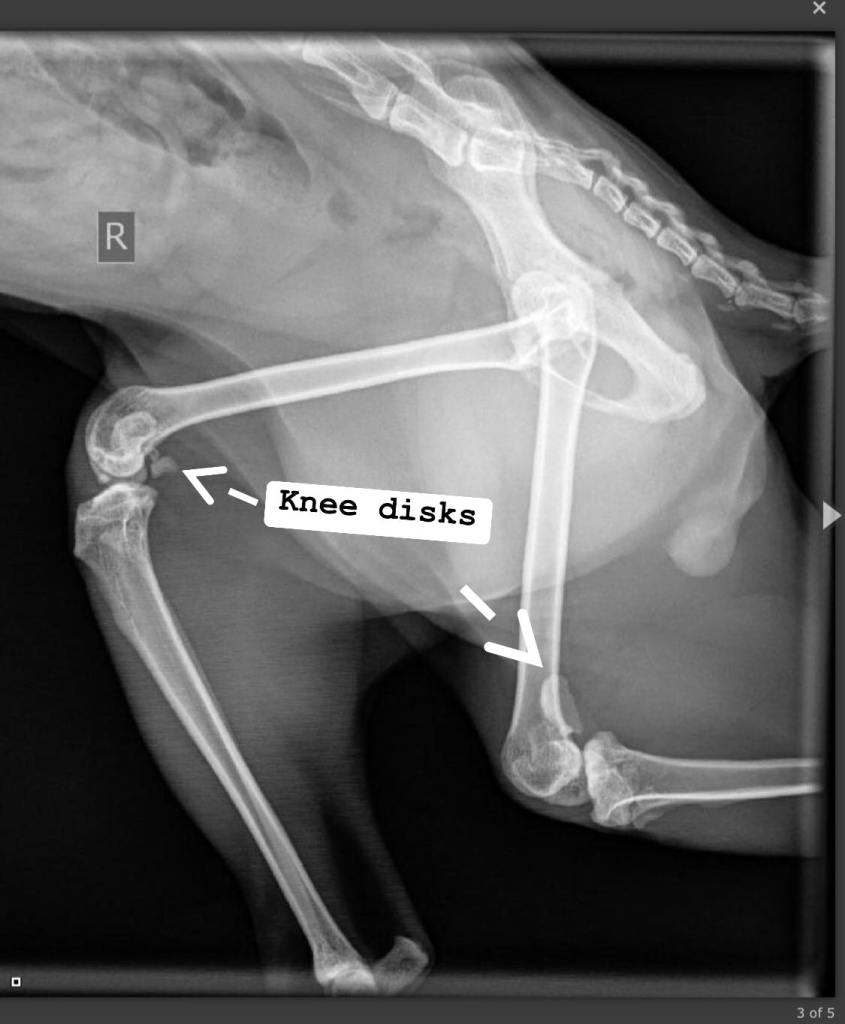

Toen Hummus bij ons kwam, droeg hij een zwaar (medisch) verleden met zich mee. Het vermoeden is dat hij als vok kater in Egypte is gebruikt. Hij had een dubbele graad 4 patella luxatie wat betekent dat zijn knietjeslos aan de verkeerde kant van de benen zaten. Slechts één nier werkte nog, en dat maar voor 40%. Zijn gebit was volledig verrot; elke tand deed pijn. De prognose was allesbehalve rooskleurig. Toch hebben we gekozen om hem te ontzien van zijn tanden om nog een korte, maar goede tijd te hebben.